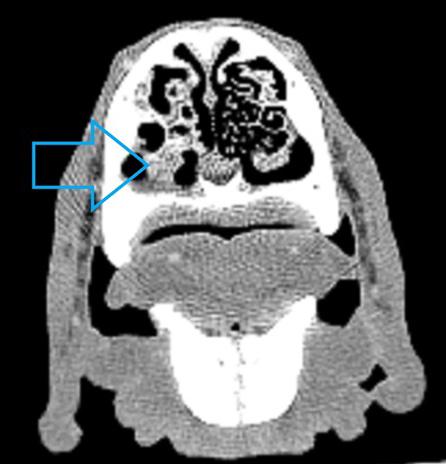

Se procedió a realizar una TC de cráneo (posicionamiento en recumbencia esternal, con 1,25 mm de corte, adquiriendo imágenes pre y postcontraste con contraste yodado Iohexol (Omnipaque 300 mg/ ml, GE Healthcare Bio-Sciences, Florida) 400 mg/kg, con algoritmo de reconstrucción de tejido blando y hueso, General Electrics Healthcare, 4 cortes, España, Madrid). En la TC se observó en la cavidad nasal izquierda una moderada destrucción de turbinetes nasales con severo engrosamiento de la mucosa nasal y presencia de tejido blando anómalo (Fig. 1A), sin presencia de masas o cuerpos extraños, ni afectación de la lámina cribiforme. Dichas lesiones se extendían al seno frontal izquierdo (Fig. 1B). A continuación, se realizó una rinoscopia (fibroscopio 5,9 mm, FujiFilm, España, Madrid) donde se observó en la cavidad nasal izquierda múltiples placas de color blanquecino con aspecto caseoso/algodonoso adheridas a la mucosa nasal con eritema y congestión asociados (Fig. 2), junto a la destrucción moderada de los turbinetes, mostrando un aspecto cavitado. La cavidad nasal derecha no presentó alteraciones. Se tomaron muestras de tejido (placa fúngica y mucosa adyacente) para cultivo y análisis histopatológico. En el cultivo se obtuvo un crecimiento de Aspergillus fumigatus, y en los resultados de la biopsia de la placa fúngica se observó un tejido eosinofílico con abundantes hifas septadas, mientras que en el tejido adyacente se evidenció una mucosa erosionada y ulcerada con abundantes neutrófilos y macrófagos con hifas fúngicas esporádicas. Como terapia se optó por la aplicación tópica intranasal de una pomada depot de clotrimazol 1 %

1. (A) Imagen de la TC de cráneo (región nasal, corte transversal en ventana de hueso postcontraste). Se observa una diferencia evidente entre la cavidad nasal derecha e izquierda, con moderada pérdida y destrucción de los turbinetes junto al engrosamiento de la mucosa y la presencia de tejido blando anómalo de la cavidad nasal izquierda (flecha azul). (B) Imagen de la TC de cráneo (región frontoorbitaria, corte transversal en ventana de hueso postcontraste). Se evidencia la presencia de engrosamiento de la mucosa y de tejido blando anómalo ubicado en el seno frontal izquierdo (flecha roja).